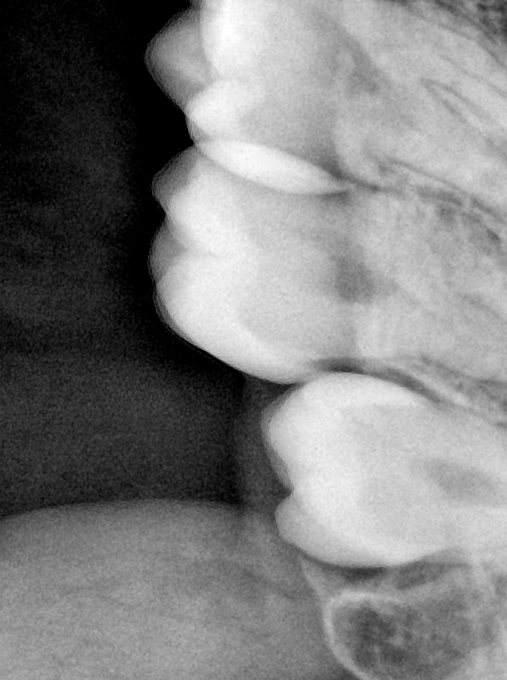

CR/DR 牙齿分割阶段记录

当前进展

- 完成了 CR/DR 牙齿相关分割训练

- 当前结果已经达到阶段预期,但仍有细节问题需要继续处理

相关测试

遇到的问题

- 训练过程中出现过 mask 下移问题

- 部分结果会出现 box 填充异常

- mask 边缘仍然有比较明显的锯齿感

参考

第二版算法问题测试